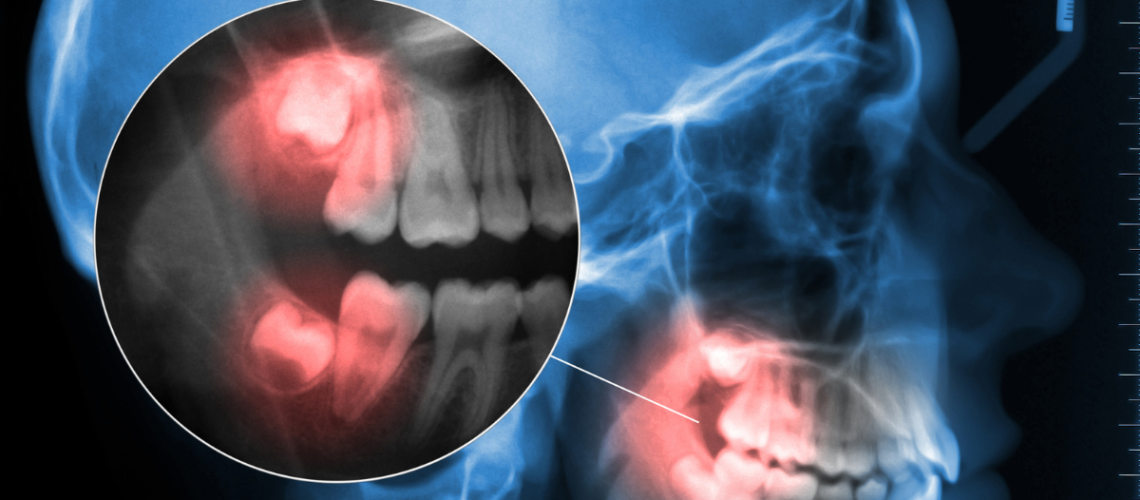

En consulta, el diagnóstico se realiza mediante examen clínico y una radiografía panorámica o TAC, que permite observar la posición exacta del diente y su relación con el resto de estructuras orales.

Con esta información, el especialista puede valorar los riesgos potenciales y establecer un plan de tratamiento individualizado.